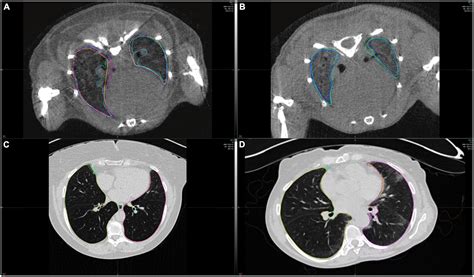

Normal Chest Ct

Receiving medical test results can be an anxiety-inducing experience, especially when it involves imaging of the torso. If you have recently undergone a scan and received a report indicating a Normal Chest CT, you might be wondering what exactly that means and why the test was performed in the first place. A computed tomography (CT) scan of the chest is a sophisticated diagnostic tool that uses X-ray equipment combined with computer processing to create detailed, cross-sectional images of your lungs, heart, airways, blood vessels, and chest wall. When a radiologist reviews these images and identifies no structural abnormalities, disease, or masses, the report is classified as normal. Understanding the significance of these findings can help alleviate concerns and clarify the next steps in your healthcare journey.

• normal chest ct scan lungs

• normal ct chest anatomy